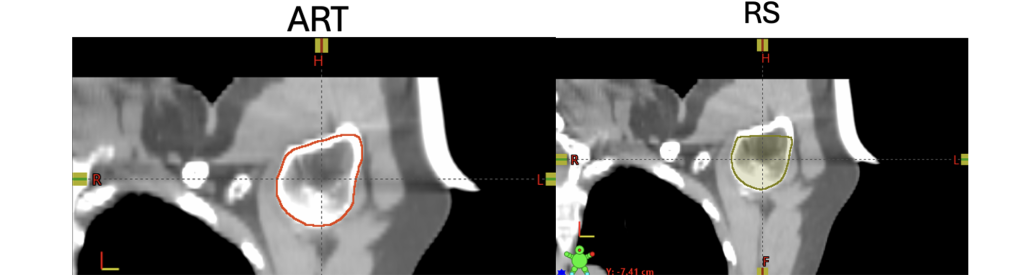

Her ser man et eksempel på at de er annerledes tegnet, hvor RS kutter inntegningen av lengre nede kranialt. Derimot så er det kaudal retning som får dose, hvor man ser at det ikke er betydelig forskjell. Dette var en årsakene vi fikk prosjektet, utforske forskjeller og si noe om disse er betydelige eller ikke, og når det eventuell bør gripes inn og korrigeres.